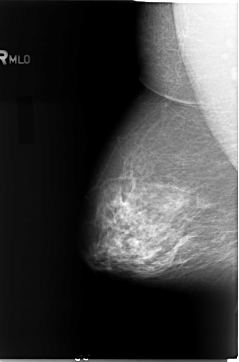

B_3080_1.RIGHT_MLO

SEQUENCE

LEFT_MLO LINES 5856 PIXELS_PER_LINE 3672 BITS_PER_PIXEL 12 RESOLUTION 50 OVERLAY

FILE: B_3080_1.LEFT_MLO.OVERLAY

TOTAL_ABNORMALITIES 1

ABNORMALITY 1

LESION_TYPE MASS SHAPE LOBULATED-IRREGULAR MARGINS ILL_DEFINED

ASSESSMENT 4

SUBTLETY 4

PATHOLOGY MALIGNANT

TOTAL_OUTLINES 1

BOUNDARY